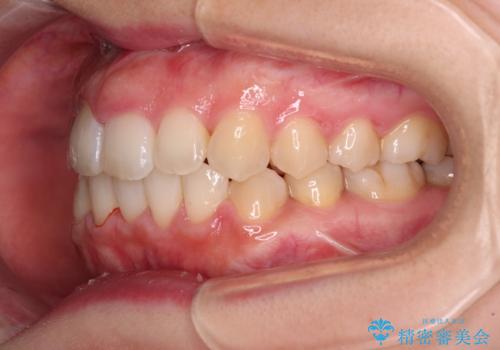

- 右上の八重歯と、左下八重歯を抜いてしまったことを気にして来院された患者様です。

下顎は既に犬歯を1本抜歯しているため、上顎右側第一小臼歯を抜歯し、ワイヤー装置にて歯列を整えることとしました。

変則的な抜歯となるため、正中と人中がずれる可能性がありましたが、仕上がりは上下正中を揃えることができました。